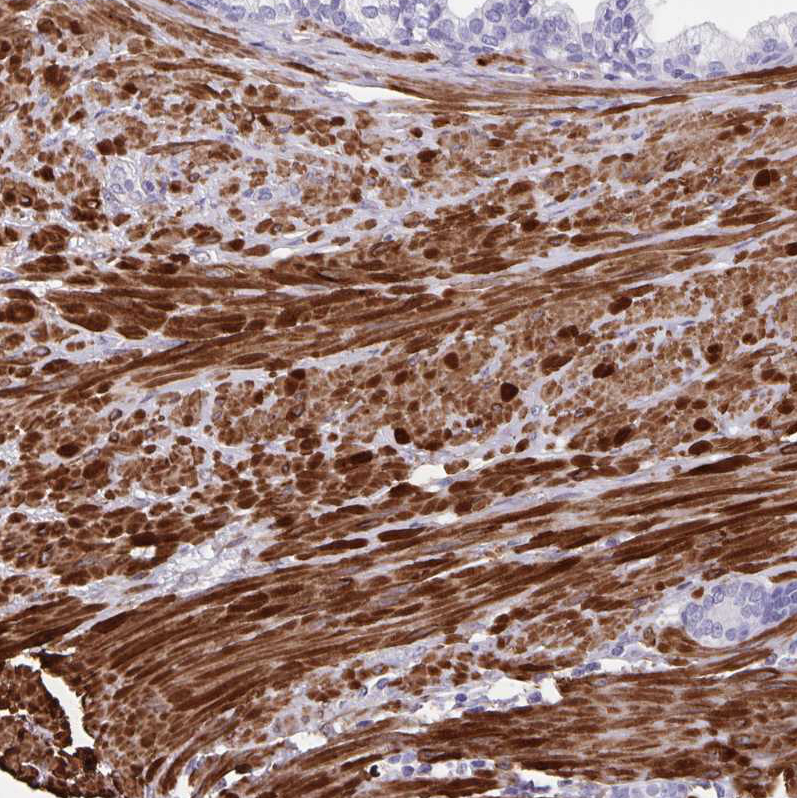

Immunohistochemistry analysis in human skeletal muscle and liver tissues using HPA040066 antibody. Corresponding SYNM RNA-seq data are presented for the same tissues.